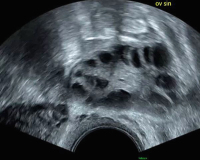

Tipps & Tricks im Gyn-Ultraschall: Wann ist PCO wirklich PCO?

Journal für Gynäkologische Endokrinologie 2017; 11 (1) (Ausgabe für Österreich): 26-28 Journal für Gynäkologische Endokrinologie 2017; 11 (1) (Ausgabe für Schweiz): 28-30 Volltext (PDF) Abbildungen